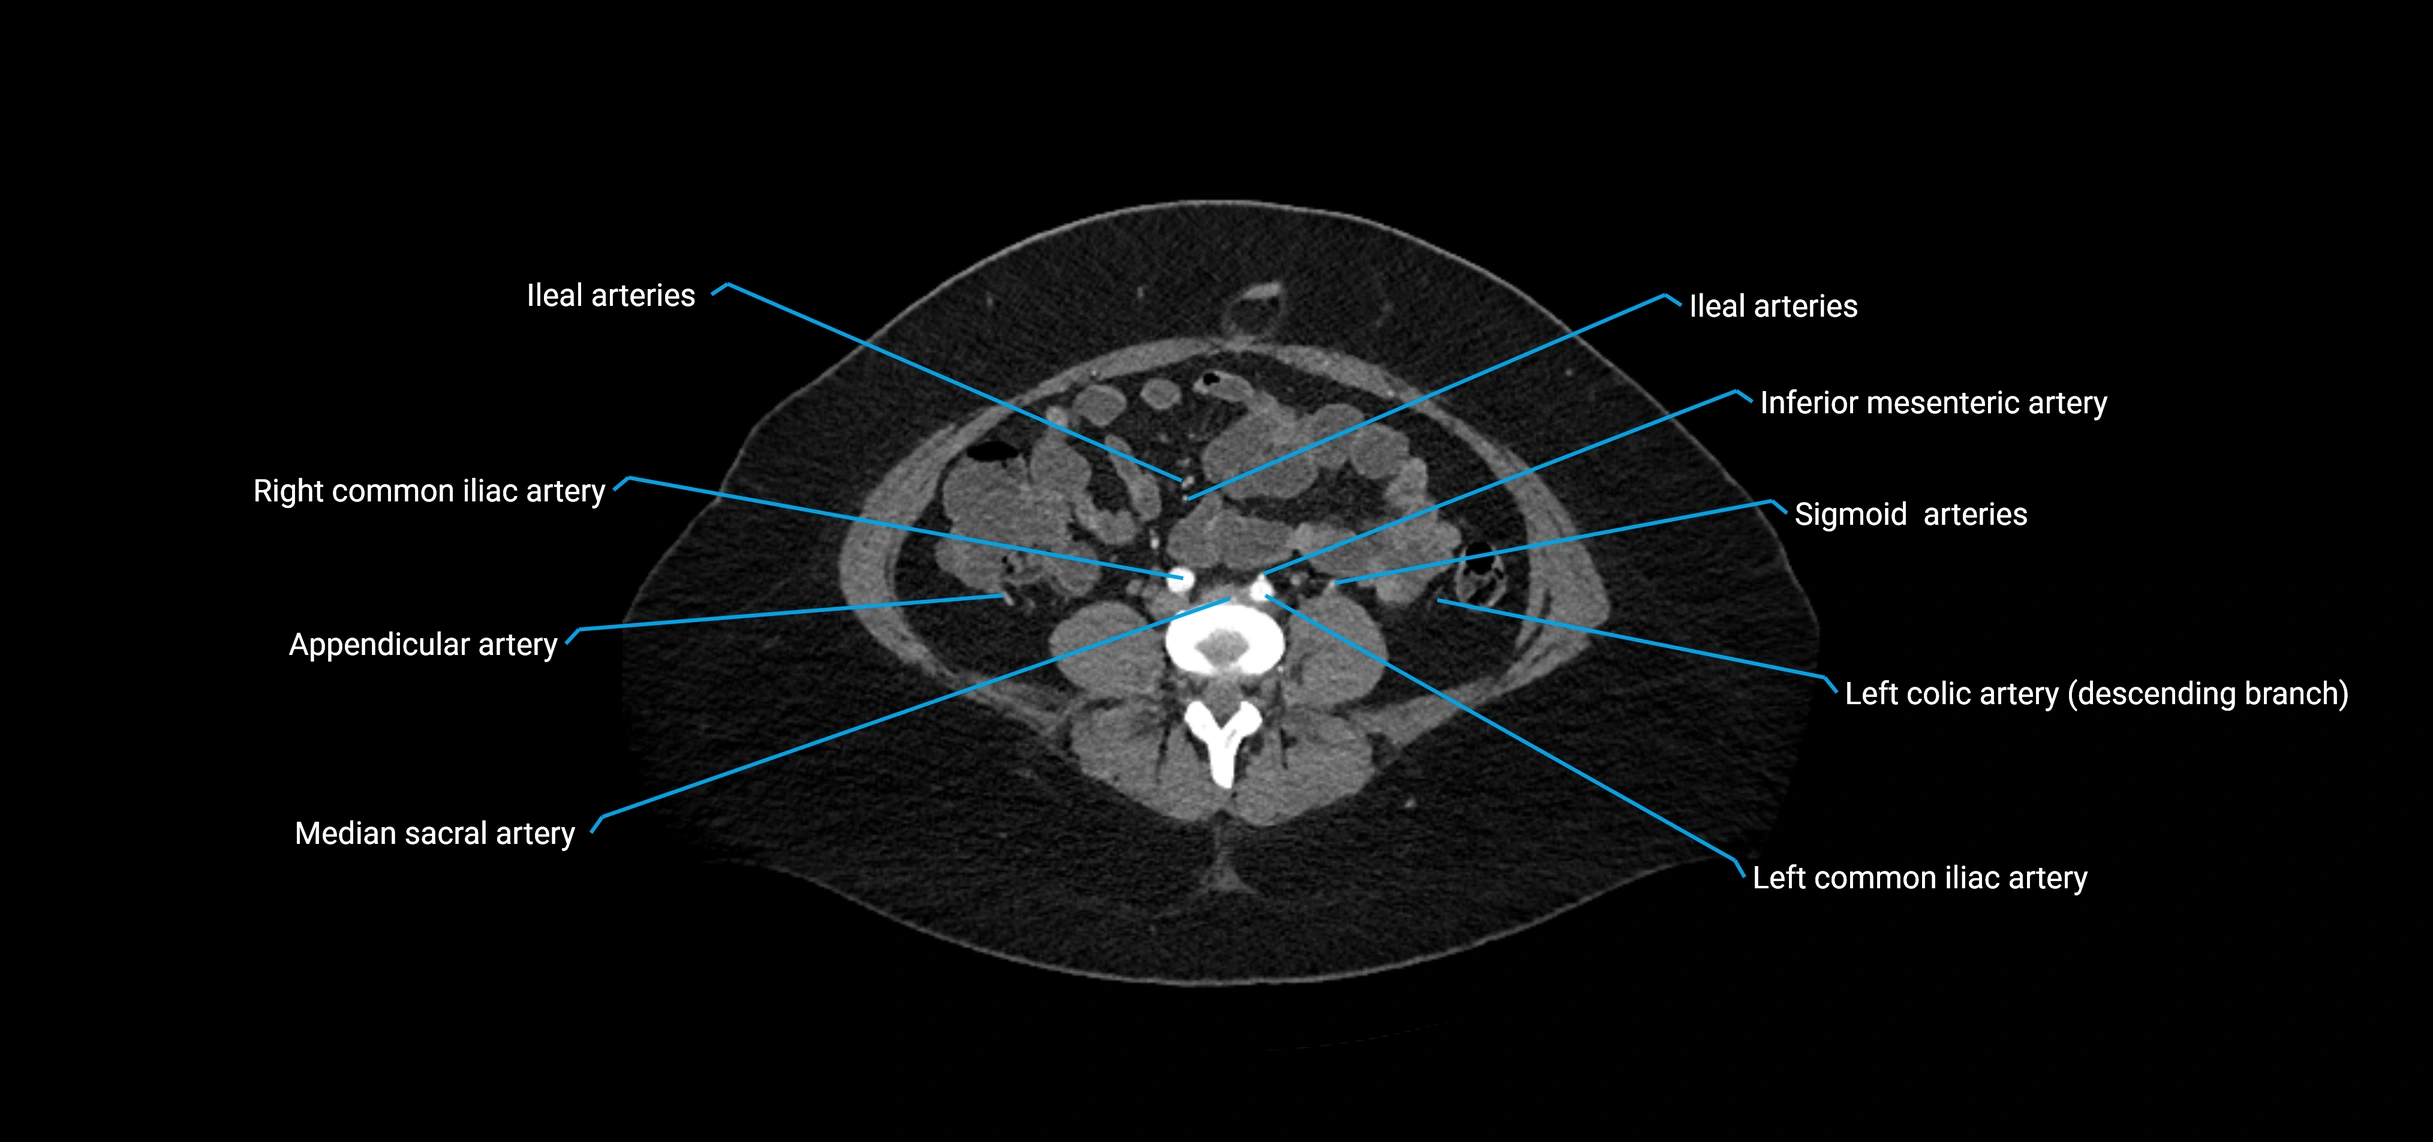

• Unpaired visceral branches: celiac trunk, superior mesenteric artery (SMA), inferior mesenteric artery (IMA)

• Paired visceral branches: middle suprarenal arteries, renal arteries, gonadal arteries (testicular or ovarian)

• Parietal branches: inferior phrenic arteries, lumbar arteries, median sacral artery

• Terminal branches: right and left common iliac arteries

Contrast-enhanced CT (CTA):

• Gold standard for abdominal aortic imaging

• Provides excellent detail of lumen, wall, aneurysm, thrombus, and branch vessels

• Multiplanar and 3D reconstructions help in aneurysm measurement, stent graft planning, and dissection evaluation

• Detects acute rupture, traumatic injury, or occlusion with high sensitivity